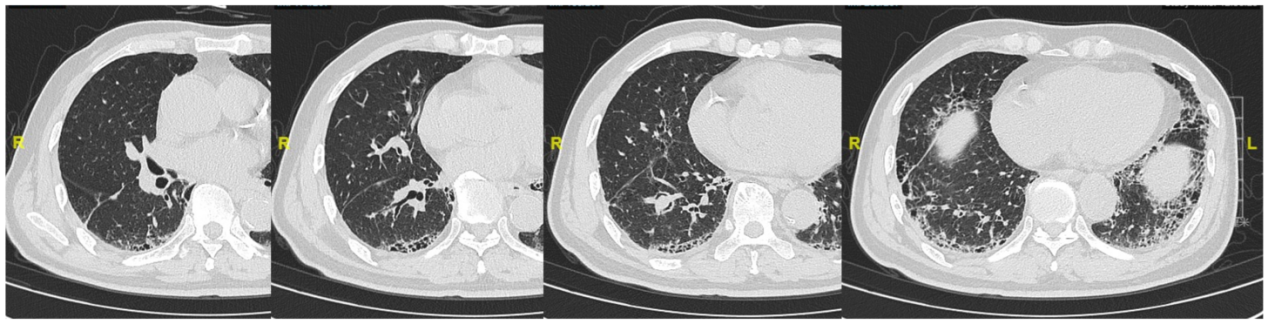

2022-05-20PET/MRI示:

1. 右肺下叶肿块(大小约62mm×41mm)及右肺门肿大淋巴结,代谢明显增高,结合病史考虑右肺下叶肺癌并右肺门淋巴结转移:右侧锁骨上区、两肺门及纵隔内淋巴结多发大小不等淋巴结,代谢轻度增高,转移不除外:

2. 右肺上叶胸膜下结节,代谢轻中度增高,转移待排;

3. 右侧局部胸膜少许结节样增厚,并少许强化,胸膜转移待排;

4. TNM分期考虑为 T4N1?M1?

5. 右侧胸腔积液,局部包裹,并右肺下叶部分萎陷:两肺下叶胸膜下间质性炎症。

图1.PET/MRI